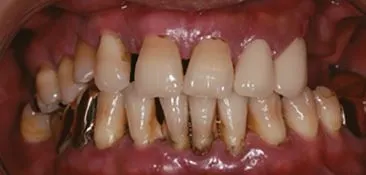

임플란트 주위염

"치아 뽑고 임플란트 하면 끝 아닌가요?" 그렇지 않다. 임플란트 역시 자연치와 마찬가지로 잇몸 질환이 생길 수 있다. 치주질환과 유사한 형태의 염증이 임플란트 주변에서 발생하는데, 이를 ‘임플란트 주위염’이라고 한다. 플라그가 쌓이면 임플란트 주변의 잇몸뼈가 서서히 녹아 결국 임플란트가 흔들리거나 빠질 수도 있다.

최근 치주과학회 공식 저널에 실린 리뷰 논문에서는 임플란트 주위질환을 일으키는 주요 위험 요인을 다음과 같이 제시한다. 가장 큰 위험 요인은 치주질환의 과거력으로, 치주질환 경험이 있는 환자는 그렇지 않은 환자보다 2.29배 높은 위험을 보였다. 또한 불량한 구강 위생관리는 임플란트 실패 위험을 3.8배 증가시키는 것으로 보고되었다. 이 외에도 당뇨, 흡연, 음주, 장기간 고용량 항흡수제 사용 등이 임플란트 예후에 부정적 영향을 미칠 수 있다. 결국, 임플란트는 시술이 끝이 아니라 관리의 시작이다. 정기적인 점검과 꾸준한 위생 관리가 임플란트를 오래, 건강하게 유지하는 가장 중요한 방법이다.